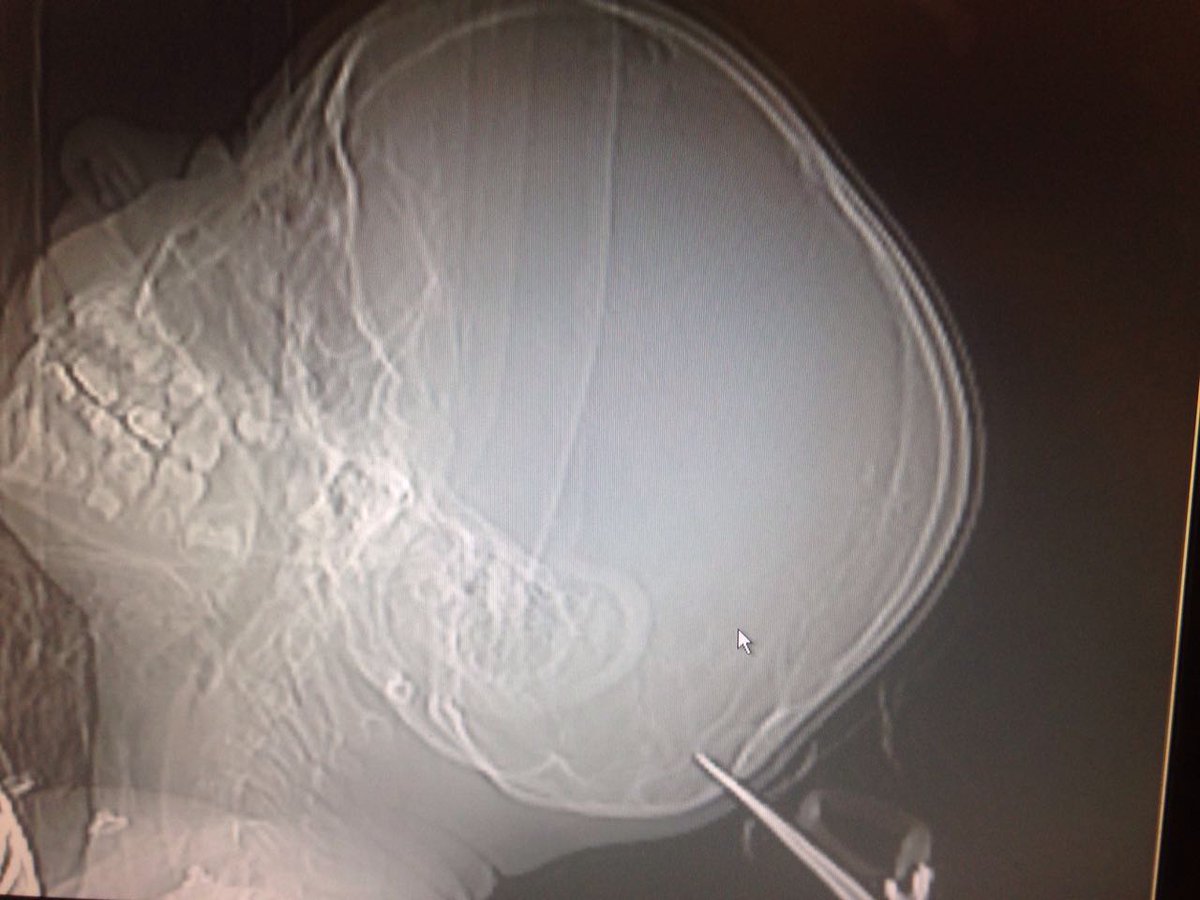

המספריים ננעצו בגולגלתו של הילד כאשר הוא ואחותו היו לבד בביתם, ובמהלך מריבה ביניהם היא זרקה אותן עליו. אחראי מיון ילדים במרכז הרפואי, ד״ר איתמר מונצ׳ק, מסר: ״מצבו של הילד מוגדר בינוני. המספריים חדרו לעצם הגולגולת, אך לאחר בדיקות לא נמצא דימום מוחי. הטיפול בו נמשך בחדר המיון״.

כעת, המספריים שננעצו בעומק של כמה ס״מ הוצאו מראשו, והילד בן השבע הועבר למחלקת כירורגיית ילדים כשמצבו מוגדר יציב.